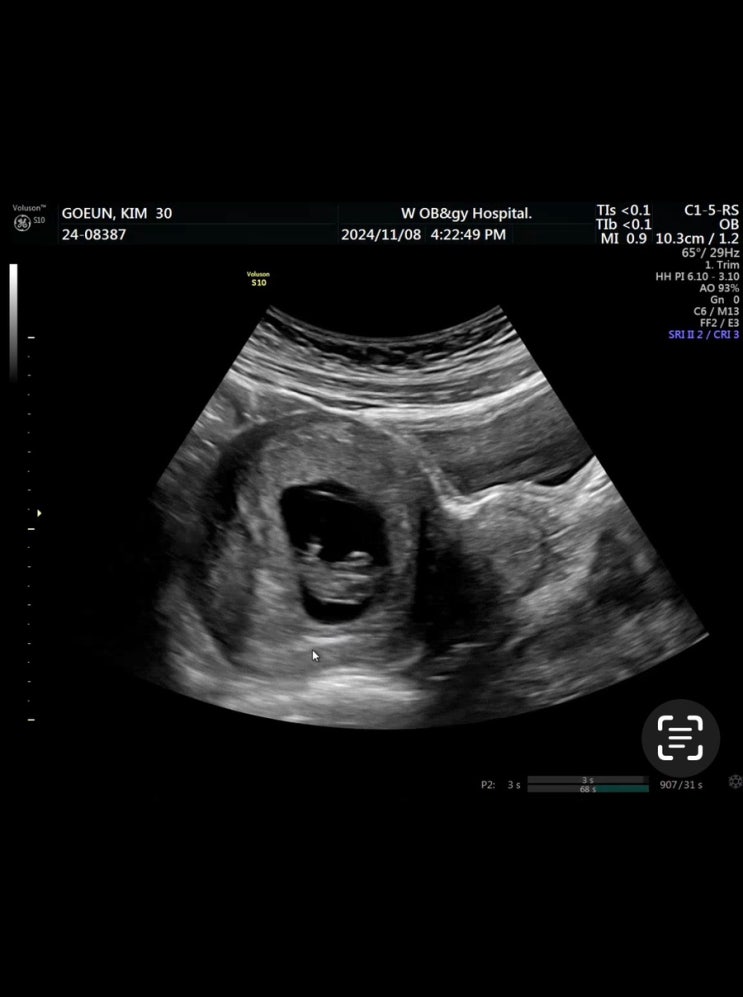

12/29-1/10 임신일기16-17주 혼자있던 시간이 많았던 연말

12/14-12/28 임신일기 14-15주 반짝이 성별은~?

12/1-12/13 임신일기 12주-13주 컨디션 회복과 함께 도파민 찾는중

11/16-11/30 임신일기 10주-11주 나 왜 임산부야.. 임신증상 우울증?

11/3-11/15 8주-9주 임신일기 아무래도 눈물버튼 고장난듯

10/21-11/2 임신일기 6~7주차 입덧 왓다가셨나요? 반짝이 심장소리듣고 눙물 왈칵스 ..